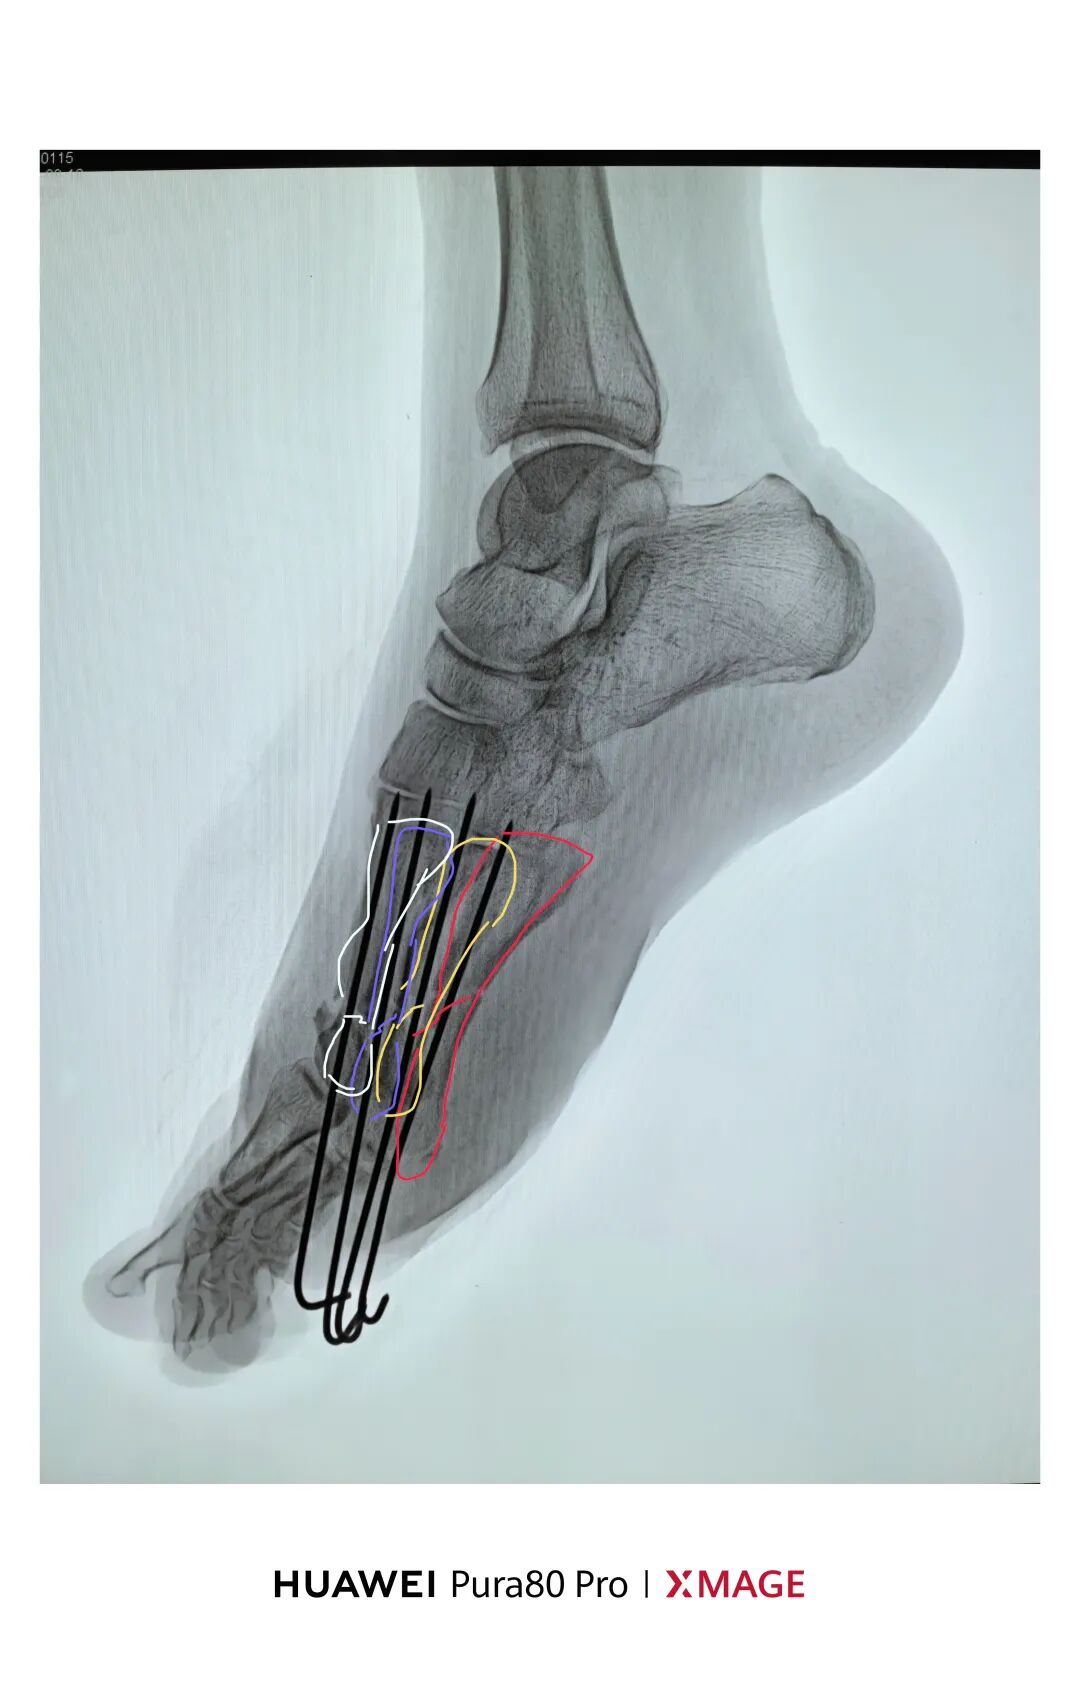

跖骨骨折常伴严重软组织损伤,治疗需兼顾骨性稳定与软组织保护。逆行髓内克氏针技术以微创方式实现有效内固定,尤其适用于多发骨折、开放损伤或软组织条件差的患者。其操作简便、血运破坏少,在损伤控制中展现独特优势。本文通过四例典型病例,探讨该技术在闭合性、开放性及严重毁损伤中的临床应用价值。

闭合性2-5跖骨骨折

逆行髓内针